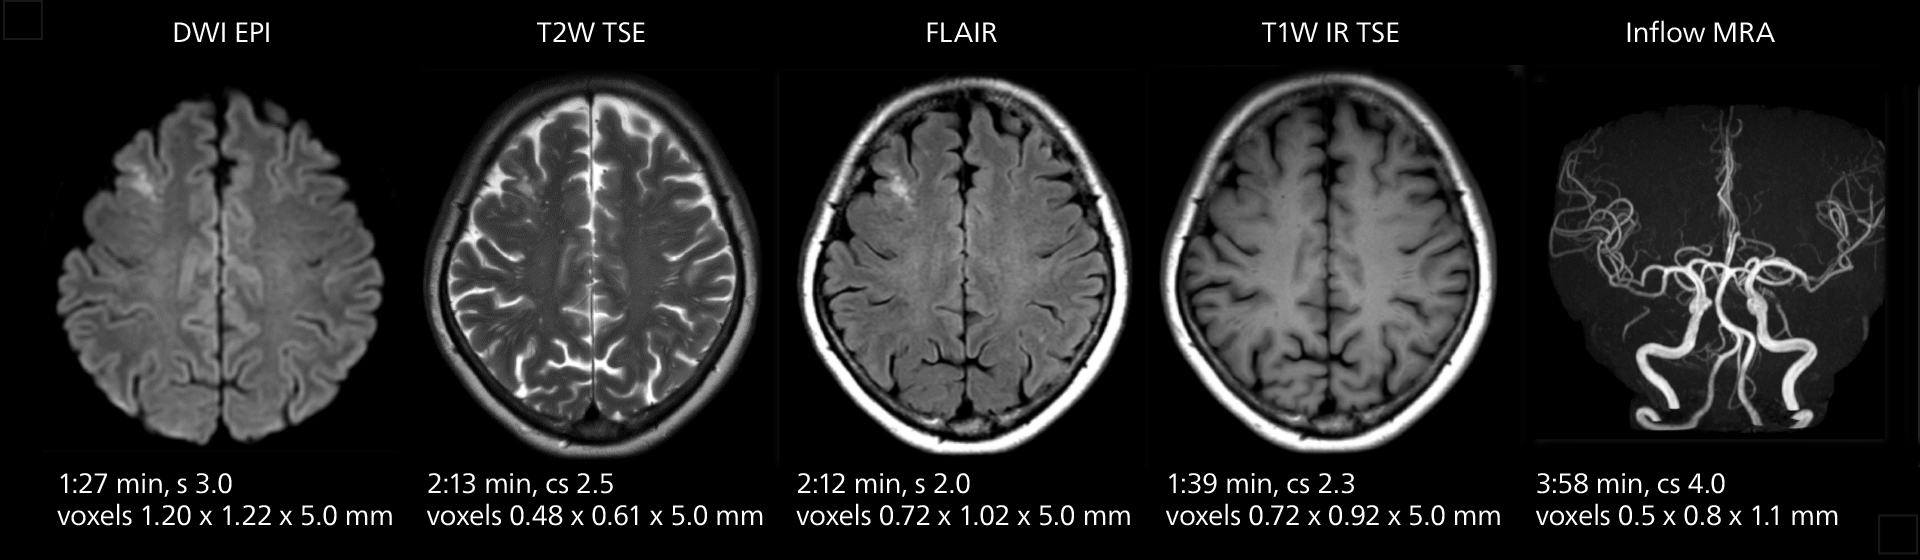

These images of an old cerebral infarction demonstrate the speed and image quality after upgrading to Elition X.

Crisp images are obtained with high resolution and short scan times using Elition X. A cyst can be seen.